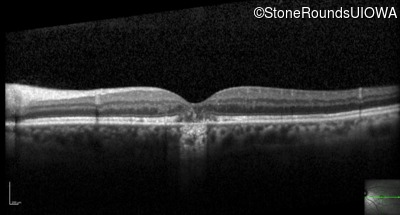

Optical Coherence Tomography - Right - 20/25 +2

Exemplar / OCT Stack